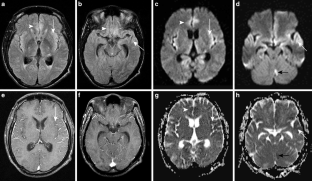

The CNS TB can be manifested (1) diffuse as tuberculous meningitis (TBM), (2) localized as tuberculoma or (3) tuberculous abscess or (4) in extradural and intradural spinal infections. Information on clinical presentation, underlying pathology and the distinguishing features is demonstrated. The TBM is further described, which may lead to cranial nerve palsy, hydrocephalus and infarction due to associated arteritis of the basal perforators. The differential diagnoses are vast and include other infections, such as bacterial, viral or fungal meningoencephalitis, malignant causes or systemic inflammation with CNS. Complicating factors of diagnosis and treatment are HIV coinfection, multi-drug resistance and TB-associated immune reconstitution inflammatory syndrome (IRIS).